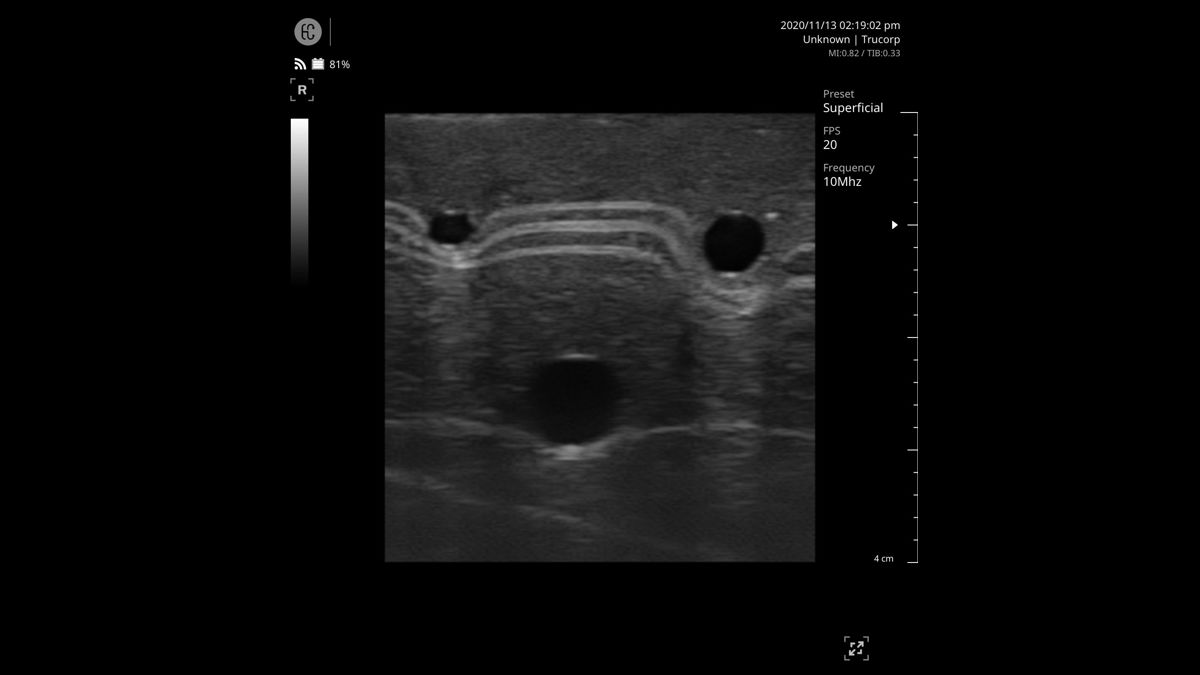

The manufacturer recommends using a size 20G needle for intravenous cannulation. While you can use any appropriate needle for practice, do not use anything larger than 18G, as this may damage the model and void your warranty.

- Prime with artificial blood – prepare approximately 200ml of concentrated blood (available separately) and fill the two vein compartments as per the user manual

- Apply ultrasound gel – apply gel to the block and/or probe as required